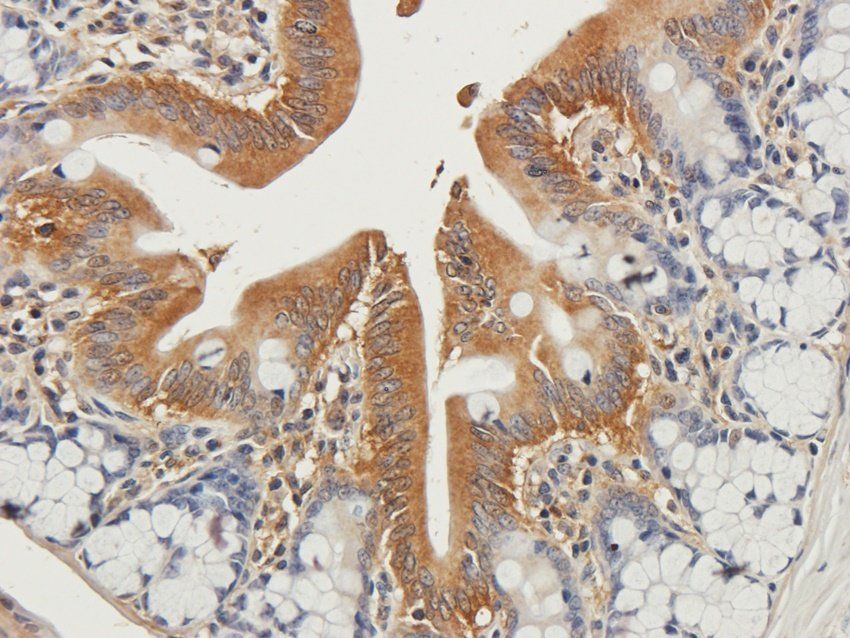

Immunohistochemical staining of rat colon tissue using anti-GYG1 (2.5 ug/ml)